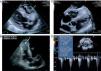

The patient was admitted with a diagnosis of community-acquired pneumonia. However, there was no therapeutic response to a series of different antibiotic regimens, and his general condition progressively deteriorated. Transthoracic echocardiography was accordingly performed (Siemens Acuson SC2000; 8V3c transducer), which showed a large infiltrating mass (45mm×40mm) in the apex of the right ventricle (RV), extending over the interventricular septum and the whole of the RV free wall up to the outflow tract (Figure 2). The mass was echogenic, with clearly defined edges and heterogeneous texture, but no sign of vascularization on color Doppler flow study. Despite slightly accelerated flow in the RV outflow tract, it did not cause significant obstruction (Figure 2D). Biventricular systolic function was preserved.

Transthoracic echocardiography (A–D), showing an infiltrating mass in the right ventricle (arrow), involving the entire apical region, interventricular septum and free wall, but not causing significant right ventricular outflow tract obstruction (D). AD: right atrium; AE: left atrium; SIV: interventricular septum; VD: right ventricle; VE: left ventricle.